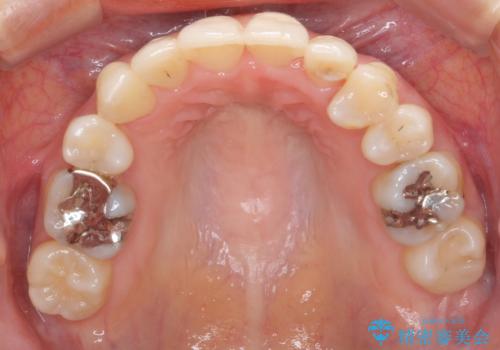

また、右上の7番(一番後ろの歯)の状態が悪く、根尖病変がありました。根の治療をする選択肢もありましたが、歯質も薄く、予算的にも治療が難しかったため、抜歯して親知らずを並べています。

左下6番(後ろから2番目の歯)も状態が悪かったため抜歯してブリッジにしています。

矯正治療をしたことで根の向きが治り、神経を取らずにブリッジにすることができました。